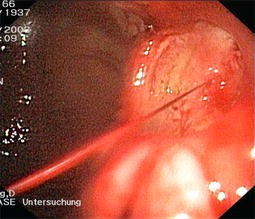

Abb. 3